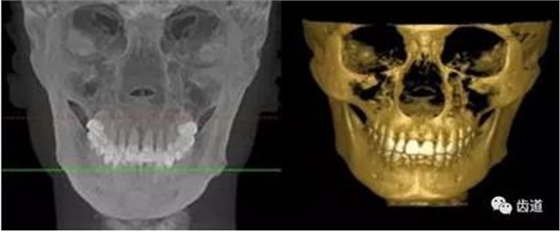

CBCT在口腔腫瘤和顳下頜關(guān)節(jié)疾病的診斷與治療及口腔整形美容易達(dá)成理解和配合,提高患者對(duì)牙病治療的接受程度和滿意度,為口腔臨床教學(xué)和科研提供必要的信息資料,與根尖片、全景曲面斷層對(duì)比更為優(yōu)越突出。

1、頜骨腫瘤

下頜骨占位病變影像

2、整形美容

整形美容假體測(cè)量應(yīng)用影像